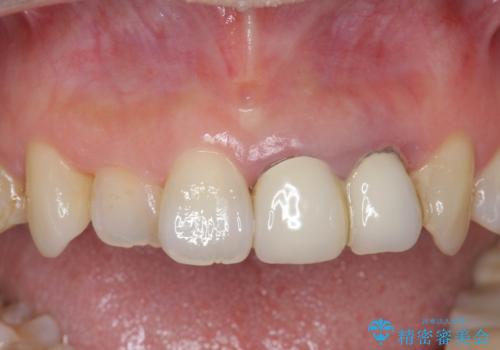

精度、周囲の歯の色調にこだわったオールセラミックブリッジを作製し、しっかりと機能・審美性を改善することができました。